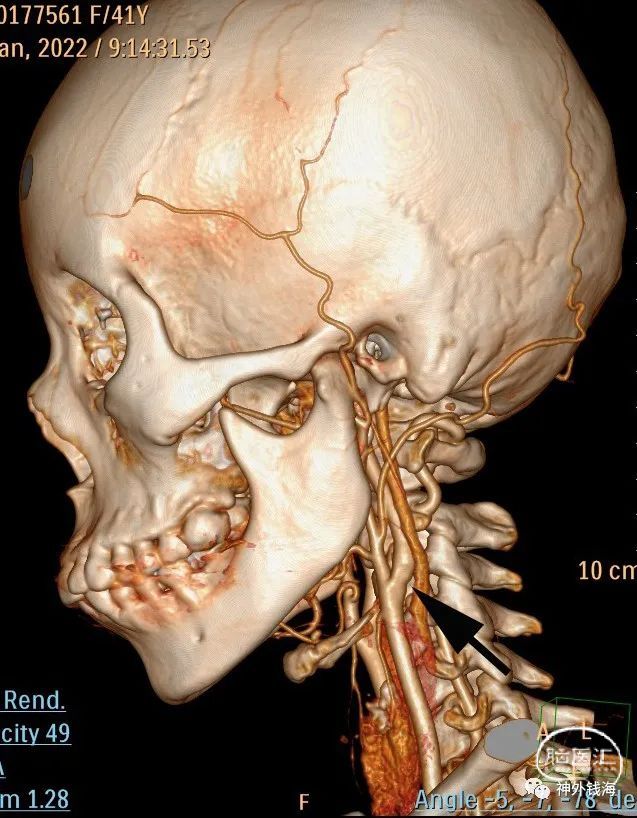

图1 患者头颈部CTA,可见左侧颈内动脉起始部轻度狭窄,狭窄程度约20%。如箭头所示。如果仅仅从狭窄程度来讲,此病例符合内科药物治疗的指征。